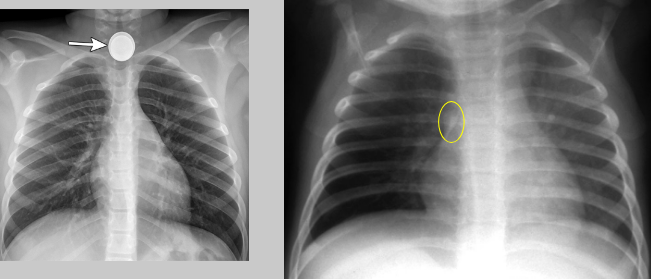

What disorder involves the aspiration of solid foreign bodies into the bronchial tree?

intrabronchial foreign bodies

Where: intrabronchial foreign bodies

foreign body in bronchial tree — atelectasis in lower lungs usually lower right

RA: intrabronchial foreign bodies

some are radiopaque some are not

partial obstruction: causes hyperaeration and a shift of the heart and mediastinum

complete obstruction: causes lobe of lung to collapse - if severe enough volume loss causes a shift of the heart and mediastinum towards affected side with elevation of ipsilateral hemidiaphragm

What pathology is present?

intrabronchial foreign body